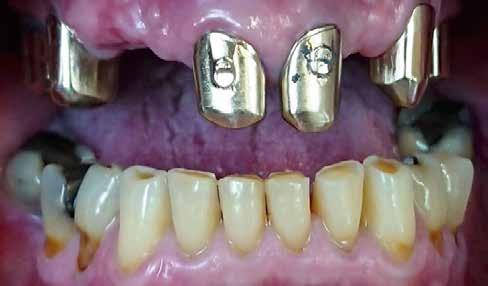

2015-ben egy 47 éves férfi páciens állkapocs-ízületi panaszai miatt kereste fel a rendelőnket. Ezen felül esztétikai problémát jelentett számára, hogy az egyik felső nagymetszőfogán lévő héj eltört (1-3. ábrák). A klinikai és radiológiai vizsgálatot követően megállapítható volt, hogy a páciens kifejezett bruxizmusa miatt csökkent a harapási magassága, és jelentős mennyiségű saját foganyagot abradált el (4. ábra)

8. ábra: Az őrlőfogak esetében nem volt szükség foganyag elvételre. Az alsó metszőfogak minimál invazív módon lettek előkészítve, a felső frontfogak esetében megőriztük az eredeti csiszolt csonkok formáját. 7. ábra: Két évvel később, a végleges helyreállítás megkezdése előtt készített felvétel (2017).